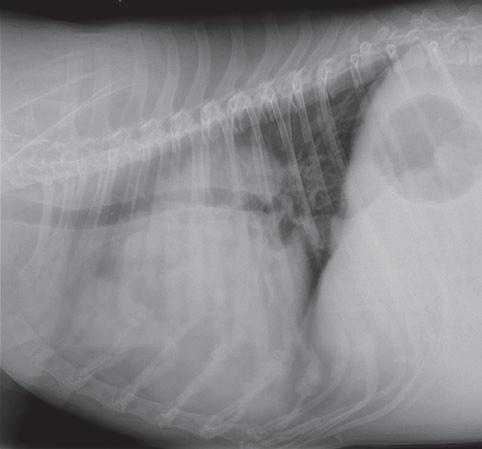

• Síndrome dígito-pulmonar felino como consecuencia de metástasis de neoplasias pulmonares primarias

• Abordaje clínico del quemodectoma de cuerpo aórtico

• Extirpación quirúrgica radical de un sarcoma asociado al punto de inyección (SAPI)